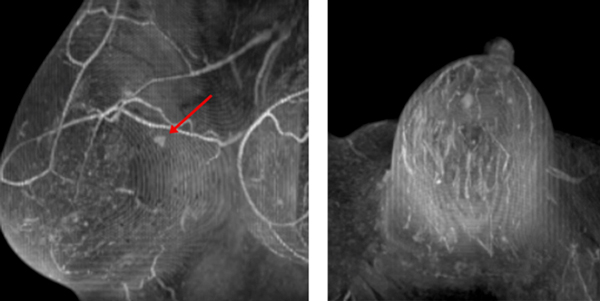

当院では2023年6月に最新の3Dマンモグラフィ装置を導入しました。従来の2Dマンモグラフィと比べて、3Dマンモグラフィはより多くの乳がんを発見できるとされています。2Dではとらえることが難しい、乳腺に重なった病変を分離して抽出することができる撮影法です。

マンモグラフィ検診で要精査と判断された微細石灰化病変の生検 が、当院で行えるようになりました。従来のステレオガイド下石灰化生 検に比べて、マンモグラフィ断層撮影を用いることで、より短時間で正確に生検を施行できます。